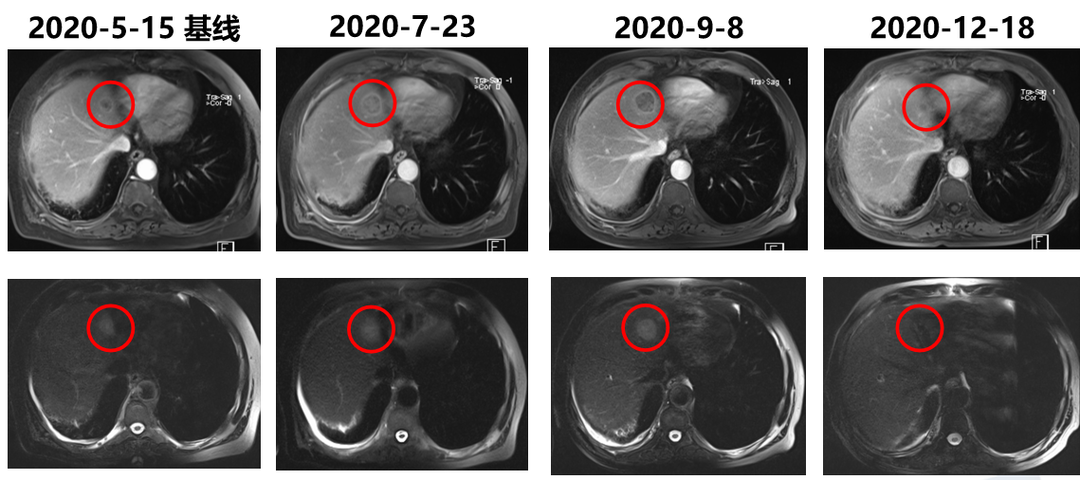

患者自2020年5月22日起开始接受替雷利珠单抗联合吉西他滨方案治疗,期间我们针对右髂骨和肝转移灶给予了放疗。6个周期联合治疗后,调整为替雷利珠单抗单药维持治疗。10个周期后疗效评价达到部分缓解(PR),至今OS已超过1年。尽管患者有多年的高血压病和2型糖尿病史,整个治疗过程仍能良好耐受,未出现严重不良反应,也未发生免疫相关不良事件。虽然结局可喜,但期间3次出现假性进展,为肿瘤治疗的决策带来了很大挑战。

患者治疗前后肝转移灶影像对比:10周期后(2020年12月18日)疗效评价达到PR